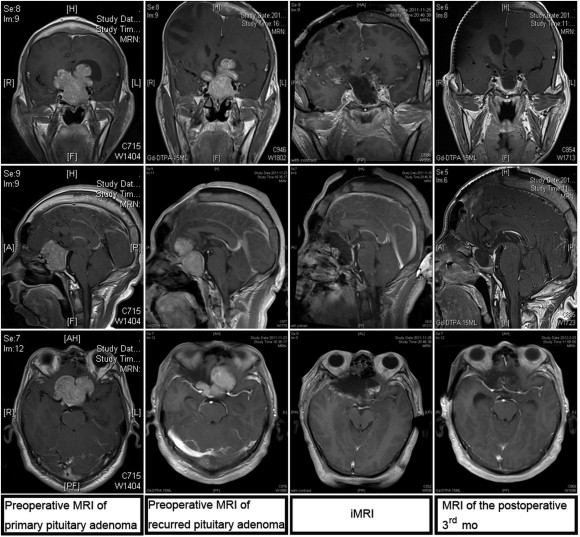

The extent of tumor resection needed was determined by iMRI examination. Residual tumor was identified in 12 cases, among which nine cases required further resection. We did not perform further resection in the remaining three cases because the tumor had extensively invaded the cavernous sinus, sphenoid sinus, and clivus, with hard or tough texture, and the extent of resection had reached the preoperative expectation. Among the nine cases that required further resection, iMRI rescanning confirmed complete resection in six cases, and subtotal resection in the remaining three (the tumor invaded the cavernous sinus and surrounded the carotid artery, and the resection range had achieved the expectation). Overall, 24 cases achieved complete tumor resection, and six cases achieved subtotal resection. The complete tumor resection rate increased from 60% to 80% (Figure 1 ;  Figure 2).

Resection of a recurred large invasive pituitary adenoma under the assistance of ...

Figure 2.

Resection of a recurred large invasive pituitary adenoma under the assistance of intraoperative magnetic resonance imaging (iMRI) using the pterion approach.